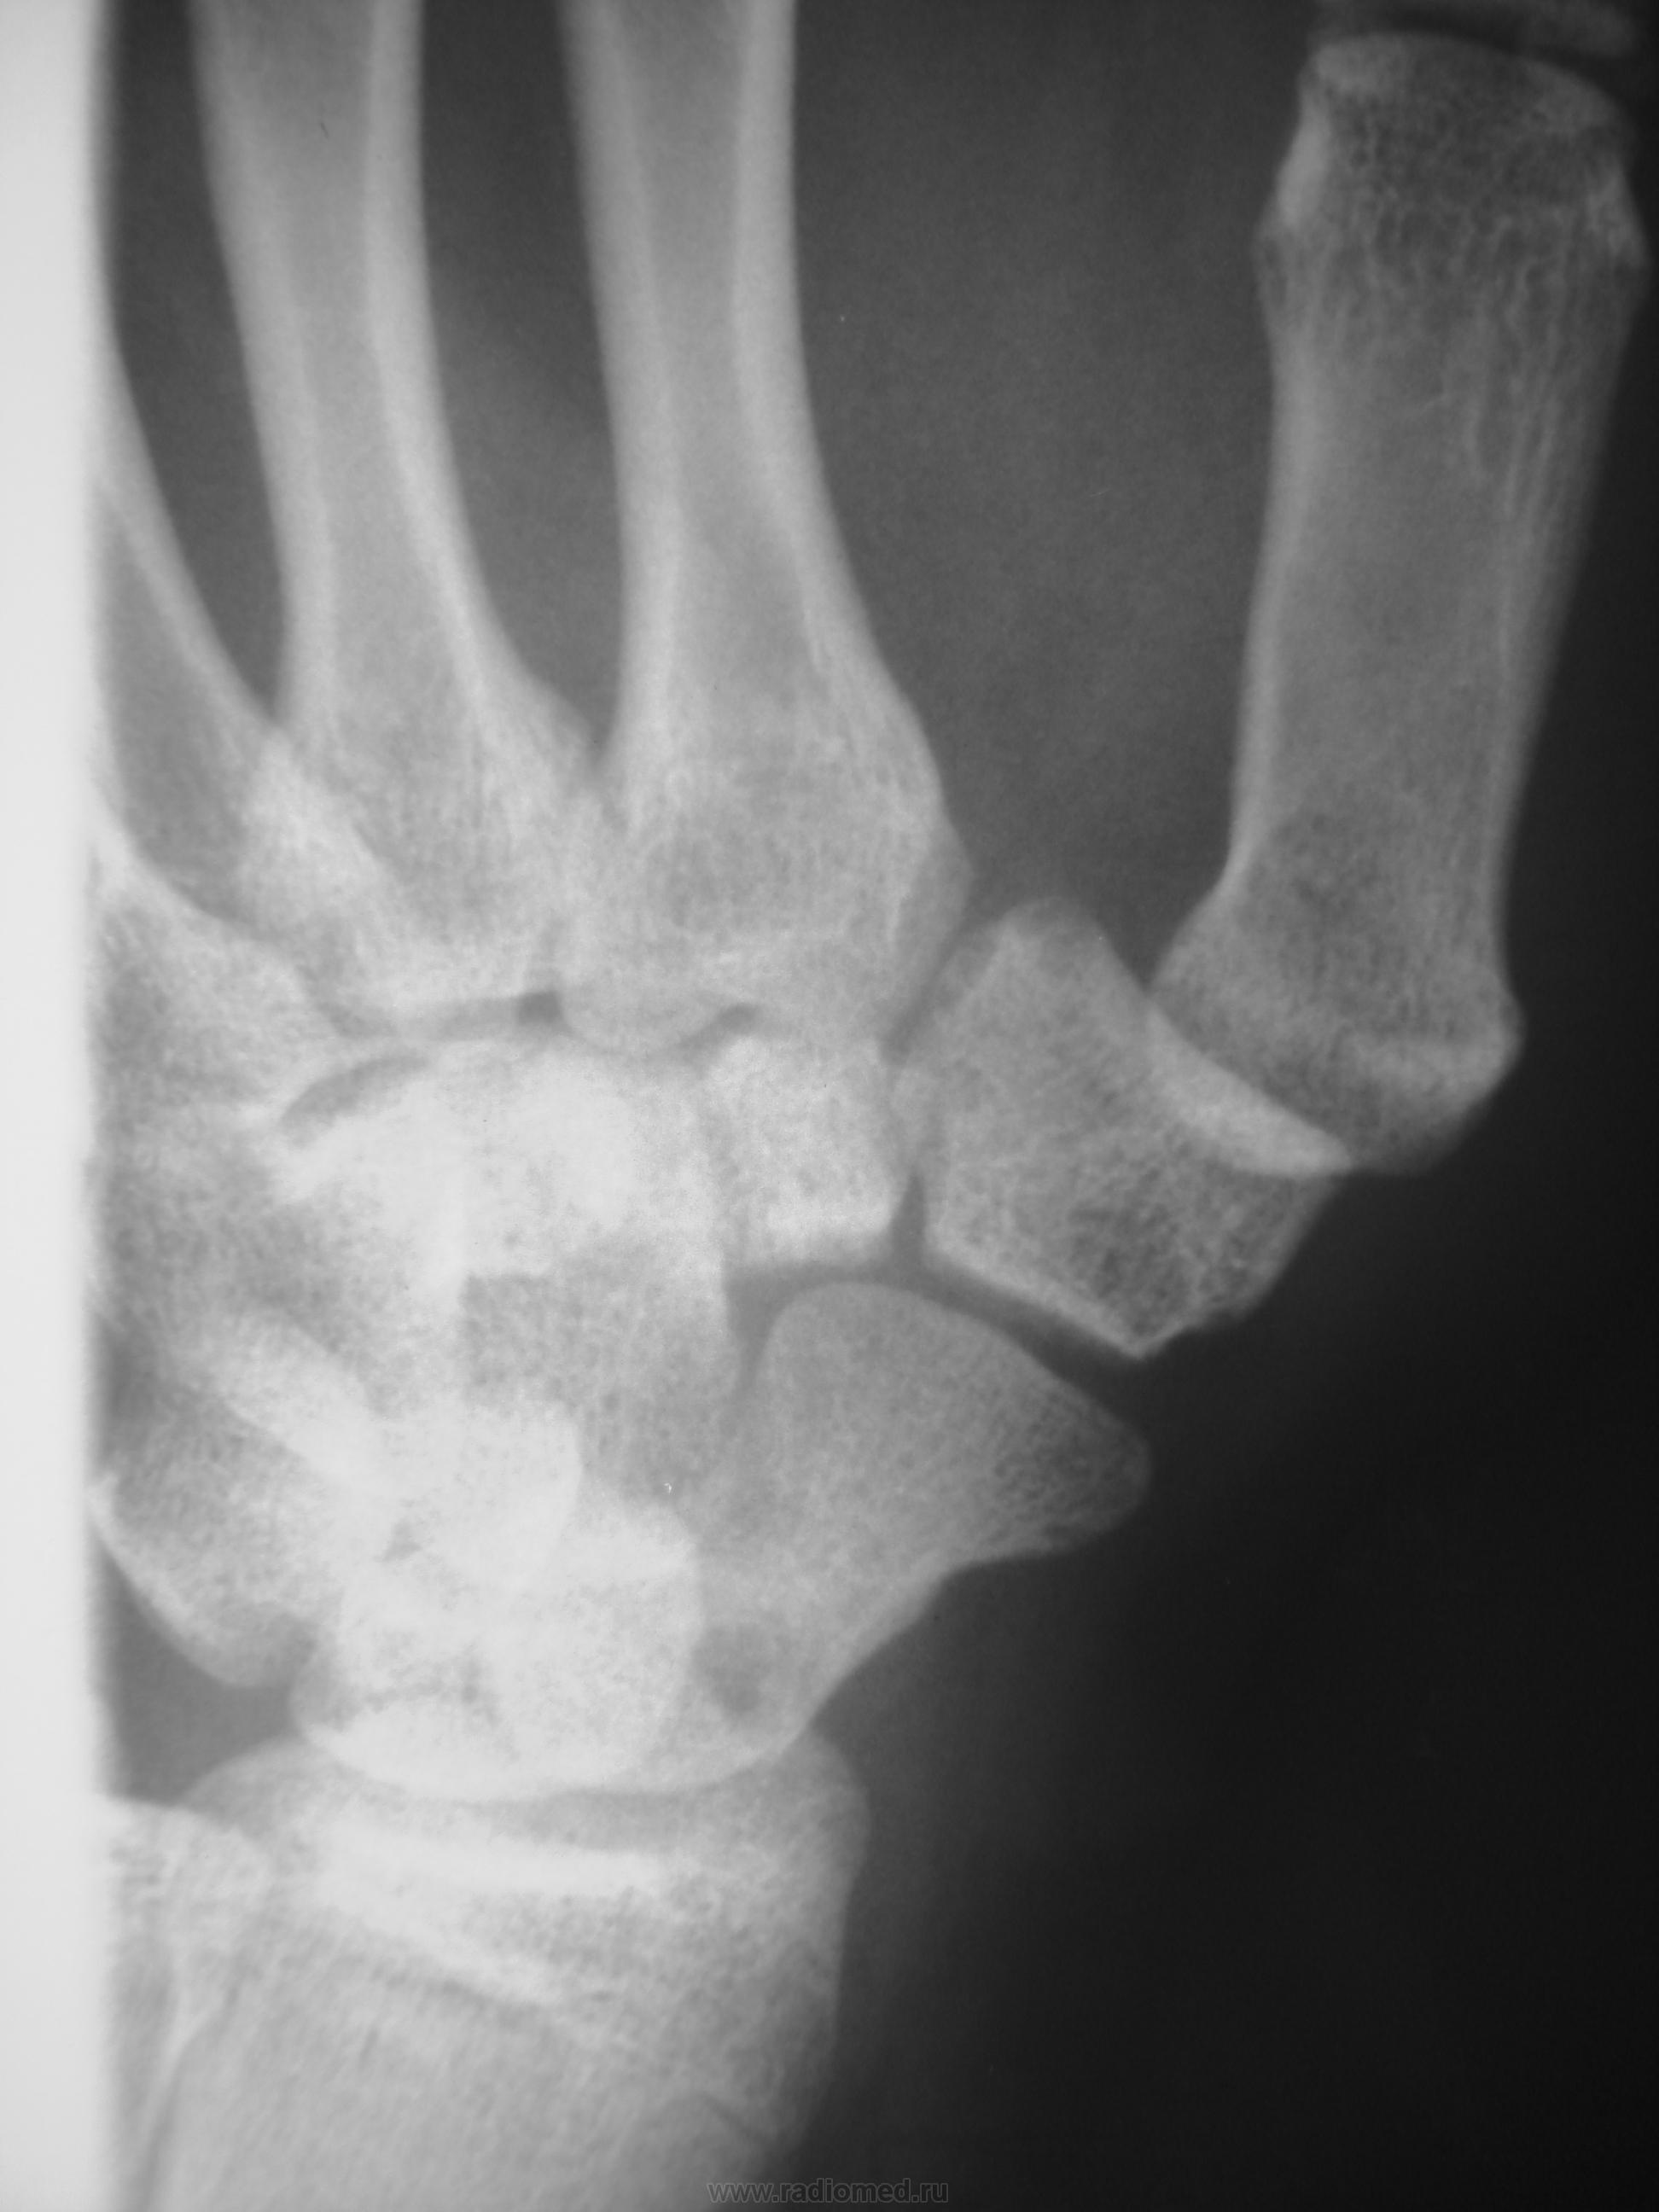

Травма в октябре 2009,сейчас появились боль, припухлость в обл. ладьевидной кости. Какие будут мнения, уважаемые коллеги?

Значит в октябре не болело. Это странно. Несросшийся перелом есть. А вот псевдартроз как-то не очень... Здесь нужна проекция для ладьевидной кости, без наслоений других.

В  октябре само сабой болело,перелом был диагносцирован,ходил в гипсе, но через месяц сняли и носили ортез. Не болело до настоящего времени.

В наших условиях - знатоки говорят о необходимости операции чуть ли не в первые 2 часа после перелома, переломы ладьи никогда не срастаются...